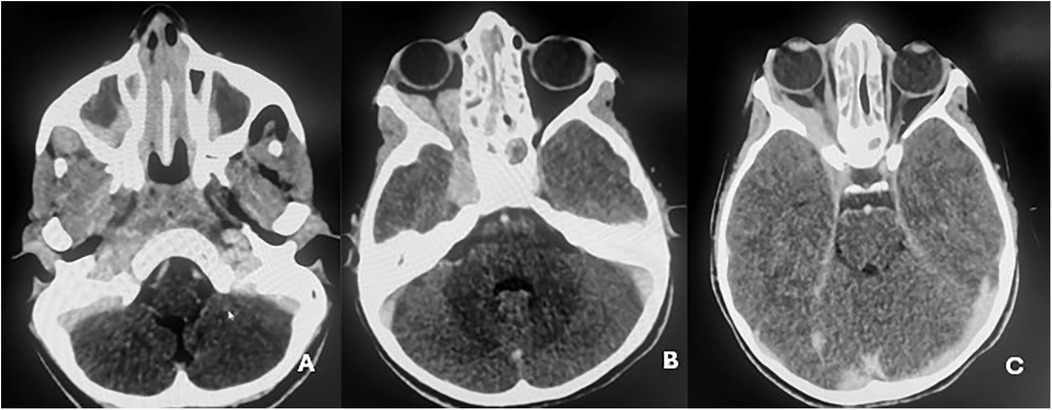

Background : Cavernous sinus tuberculosis is an extremely rare manifestation of central nervous system tuberculosis in children, with only two cases reported worldwide. It can mimic malignancy or other inflammatory conditions. Its occurrence in children with primary immunodeficiency, particularly major histocompatibility complex (MHC) class II deficiency, has not yet been described. Case report : We report an 11-year-old girl with a history of recurrent infections and chronic otitis media. She presented with right orbital swelling, severe headaches, and exophthalmos. Imaging revealed an extensive mass in the sinonasal and orbital regions, extending to the skull base and cavernous sinus. Computed tomography–guided biopsy and histopathology, supported by PCR testing for Mycobacterium tuberculosis, confirmed extensive orbital and cervicofacial tuberculosis. Immunological evaluation and genetic analysis revealed familial MHC class II deficiency. The patient received antituberculous therapy (HRZE followed by HR), leading to clinical and radiologic improvement. She continues intravenous immunoglobulin replacement every 21 days while awaiting bone marrow transplantation. Conclusions : This case highlights the importance of considering tuberculosis in atypical cavernous sinus lesions in children, especially in endemic regions. Severe or unusual infections should prompt evaluation for underlying immunodeficiency.